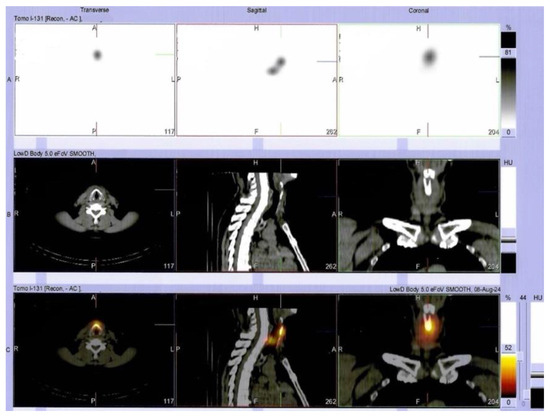

Multilayered Insights into Poorly Differentiated, BRAFV600E-Positive, Thyroid Carcinoma in a Rapidly Developing Goiter with Retrosternal Extension: From En “Y” Cervicotomy to SPECT/CT-Positive Lung Metastases

Sima, O.-C.; Cucu, A.-P.; Terzea, D.; Nistor, C.; Vasilescu, F.; Eftimie, L.-G.; Ciobica, M.-L.; Costachescu, M.; Carsote, M. Multilayered Insights into Poorly Differentiated, BRAFV600E-Positive, Thyroid Carcinoma in a Rapidly Developing Goiter with Retrosternal Extension: From En “Y” Cervicotomy to SPECT/CT-Positive Lung Metastases. Diagnostics 2025, 15, 2049. https://doi.org/10.3390/diagnostics15162049